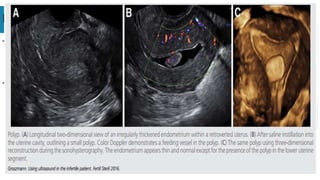

SONOHYSTEROGRAPH

Y

• It improves the delineation

of the uterine cavity

• Saline is used as contrast

• Compared to hysteroscopy,

SHG has 87.5% sensitivity,

100% specificity, for the

detection of uterine cavity

abnormality like endometrial

polyp/ fibroid & Intrauterine

adhesions

2D DOPPLER

ULTRASONOGRAPH

• Highlights the vascularity and its

distribution

• Helps detect some of the

intrauterine lesions as the

feeding vessels of polyps and the

depth of myoma .

• Helps in differentiating between

benign and malignant component

of pelvic pathology by assessing

vascular resistance.

FIBROID

• 3D ultrasound has recently been

used to map the exact location of

fibroids in relation to the

endometrial cavity and

surrounding structures.

ENDOMETRIAL POLYPS

- Assessing whether or not a

patient has an endometrial

polyp and then determine the

size of the polyp and its pedicle.

-Studies have demonstrated that

the uterine cavity, endometrial

lining and myometrium are best

visualized using

sonohysterography, and that

these images are further

improved by the use of 3D

ultrasound.